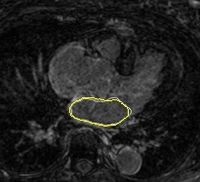

Left Atrium Wall Segmentation Using Topological FeaturesCatheter ablation has been proposed for treatment of atrial fibrillation arrhythmia. MRI data, obtained at University of Utah, are used to explore lesion ablation and scarification locations. In addition, MRI analysis may help to predict if the ablation procedure will help a patient or not. Many of these image analysis tasks are largely based on segmentation of left atrial wall, which is done manually or semi-automatically. Automatic segmentation uses moving contours or surfaces (interfaces) to segment image data by minimizing a predefined energy function. These moving interfaces are highly affected by image data, which can be thought as a force field pushing the interface to features of choice. Thus, the choice of interface attracting image features is critical. More... | |

Segmentation and Registration for Atrial Fibrillation Ablation TherapyMagnetic resonance imaging (MRI) has been used for both pre- and and post-ablation assessment of the atrial wall. MRI can aid in selecting the right candidate for the ablation procedure and assessing post-ablation scar formations. Image processing techniques can be used for automatic segmentation of the atrial wall, which facilitates an accurate statistical assessment of the region. As a first step towards the general solution to the computer-assisted segmentation of the left atrial wall, in this research we propose a shape-based image segmentation framework to segment the endocardial wall of the left atrium.More... New: Y. Gao, B. Gholami, R. S. MacLeod, J, Blauer, W. M. Haddad, and A. R. Tannenbaum, Segmentation of the Endocardial Wall of the Left Atrium using Local Region-Based Active Contours and Statistical Shape Learning, SPIE Medical Imaging, San Diego, CA, 2010. | |

Left Atrium Segmentation for Atrial Fibrillation TreatmentThe planning and evaluation of left atrial ablation procedures is commonly based on the segmentation of the left atrium, which is a challenging task due to large anatomical variations. In this paper, we propose an automatic approach for segmenting the left atrium from magnetic resonance imagery (MRI). The segmentation problem is formulated as a problem in variational region growing. More... New: L. Zhu, Y. Gao, A. Yezzi, A. Tannenbaum. Automatic Segmentation of the Left Atrium from MRI images using Variational Region Growing with a Shape Prior, IEEE Transaction on Image Processing, vol. 22, no. 12, 2013. New: L. Zhu, Y. Gao, A. Yezzi, R. MacLeod, J. Cates, A. Tannenbaum. Automatic Segmentation of the Left Atrium from MRI Images Using Salient Feature and Contour Evolution, IEEE Engineering in Medicine and Biology Conference(EMBC), 2012. | |